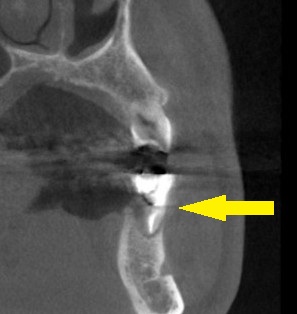

抜歯する前にCT撮影したところ、外側の骨が吸収されてしまっていた(下の写真、下段左)ので、抜歯即時インプラント埋入ではなくて、まず抜歯して、数か月治癒を待つこととしました。

抜歯後5か月でCTを撮影すると、骨はかなり再生されているのですが、骨幅やや不足していました(下の写真下段中)。